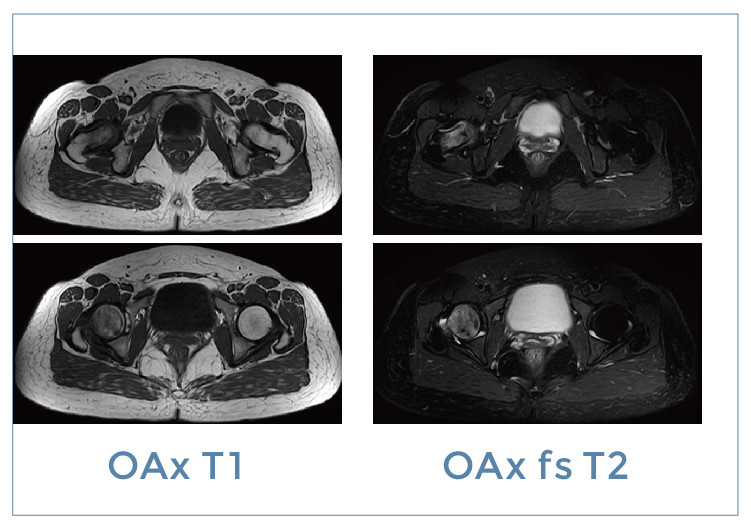

【朗润影像档案】磁共振影像病例分享(编号20200104)

【朗润影像档案】磁共振影像病例分享(编号20191229)